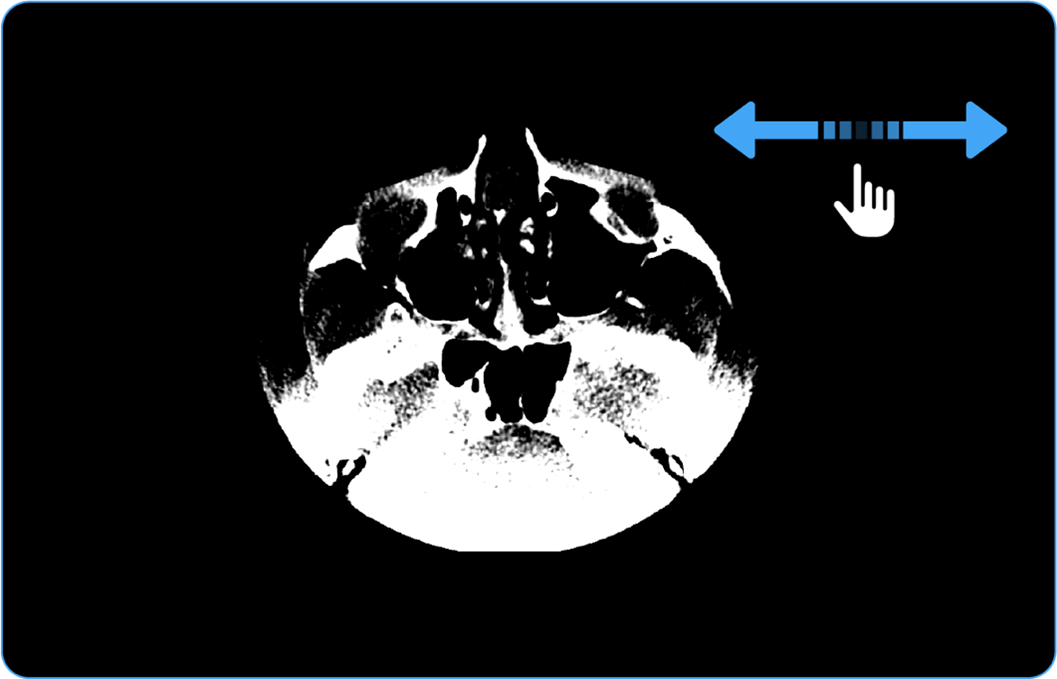

• Scroll sideways to navigate through other images in the series.